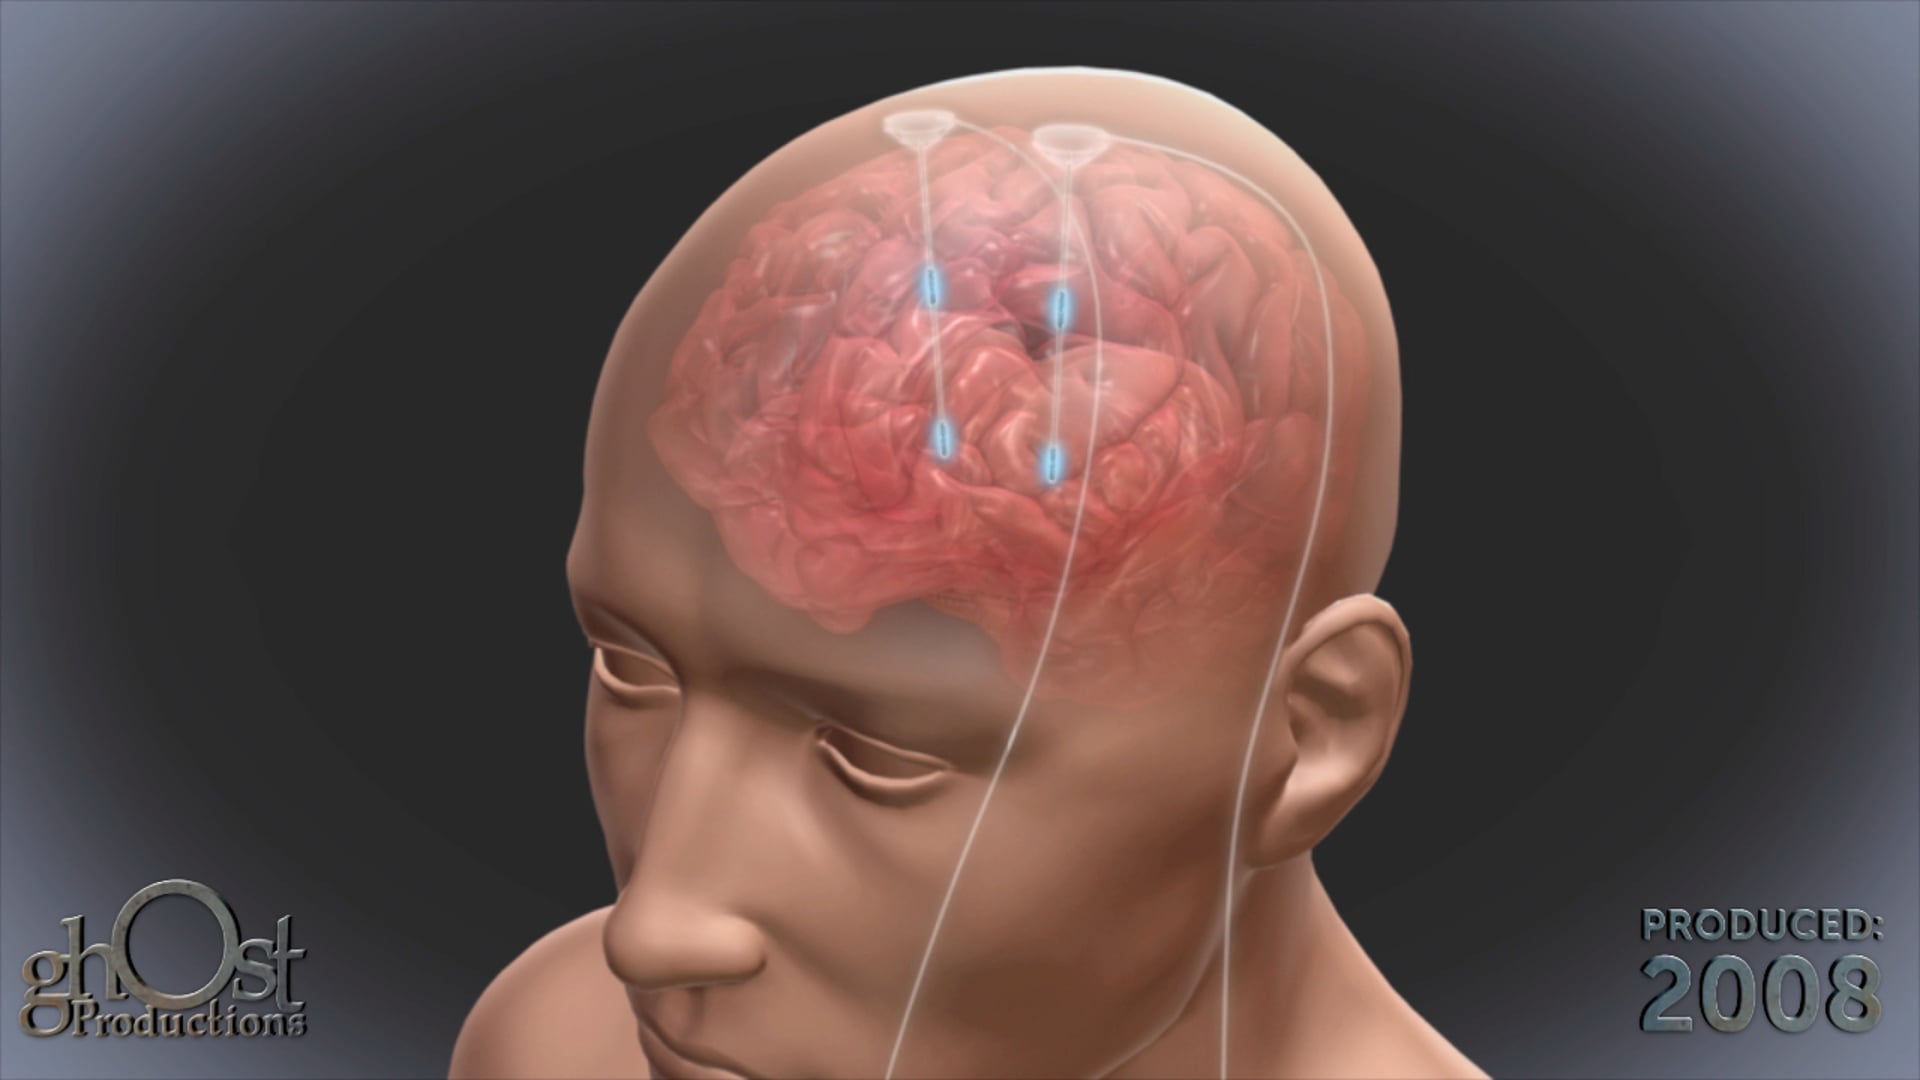

Medical Animation

Neurology

Medical Devices